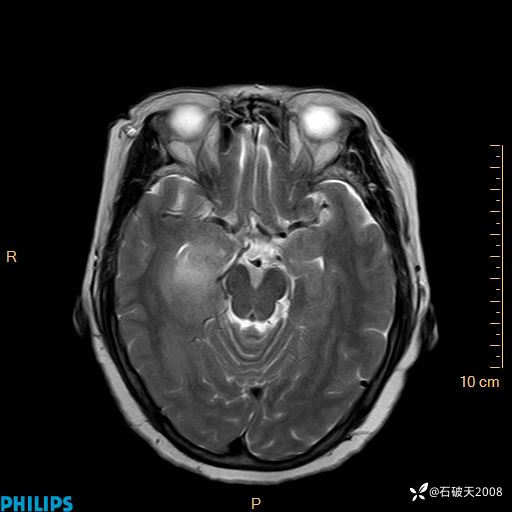

颅内占位,影像征象不是很丰富,有病理

hyy838 推荐女 62岁 主 诉:头晕12小时,加重1小时。

现病史:患者于12小时前无明显诱因出现头晕,呈持续性,无天旋地转及行走不稳,伴恶心、呕吐,呕吐共5次,呕吐物为胃内容物(具体性质不详),无胸闷、胸痛、心慌,无腹痛、腹泻,无咳嗽、咳痰,无发热、意识不清、肢体抽搐及大小便失禁等,1小时前患者上述症状加重,未诊疗,为求进一步治疗急自行来我院,门诊以“头晕待查”为诊断收入我科,发病来,神志清,精神差,饮食、睡眠差,大小便正常,体重未见明显下降。

T1